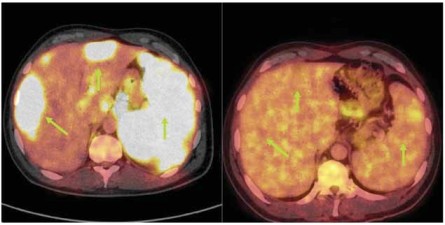

Obr. 3: Srovnání vstupního a časného 18FDG PET/CT

vyšetření provedeného po 2 cyklech chemoterapie s rituximabem u

nemocného s difúzním B-velkobuněčným lymfomem